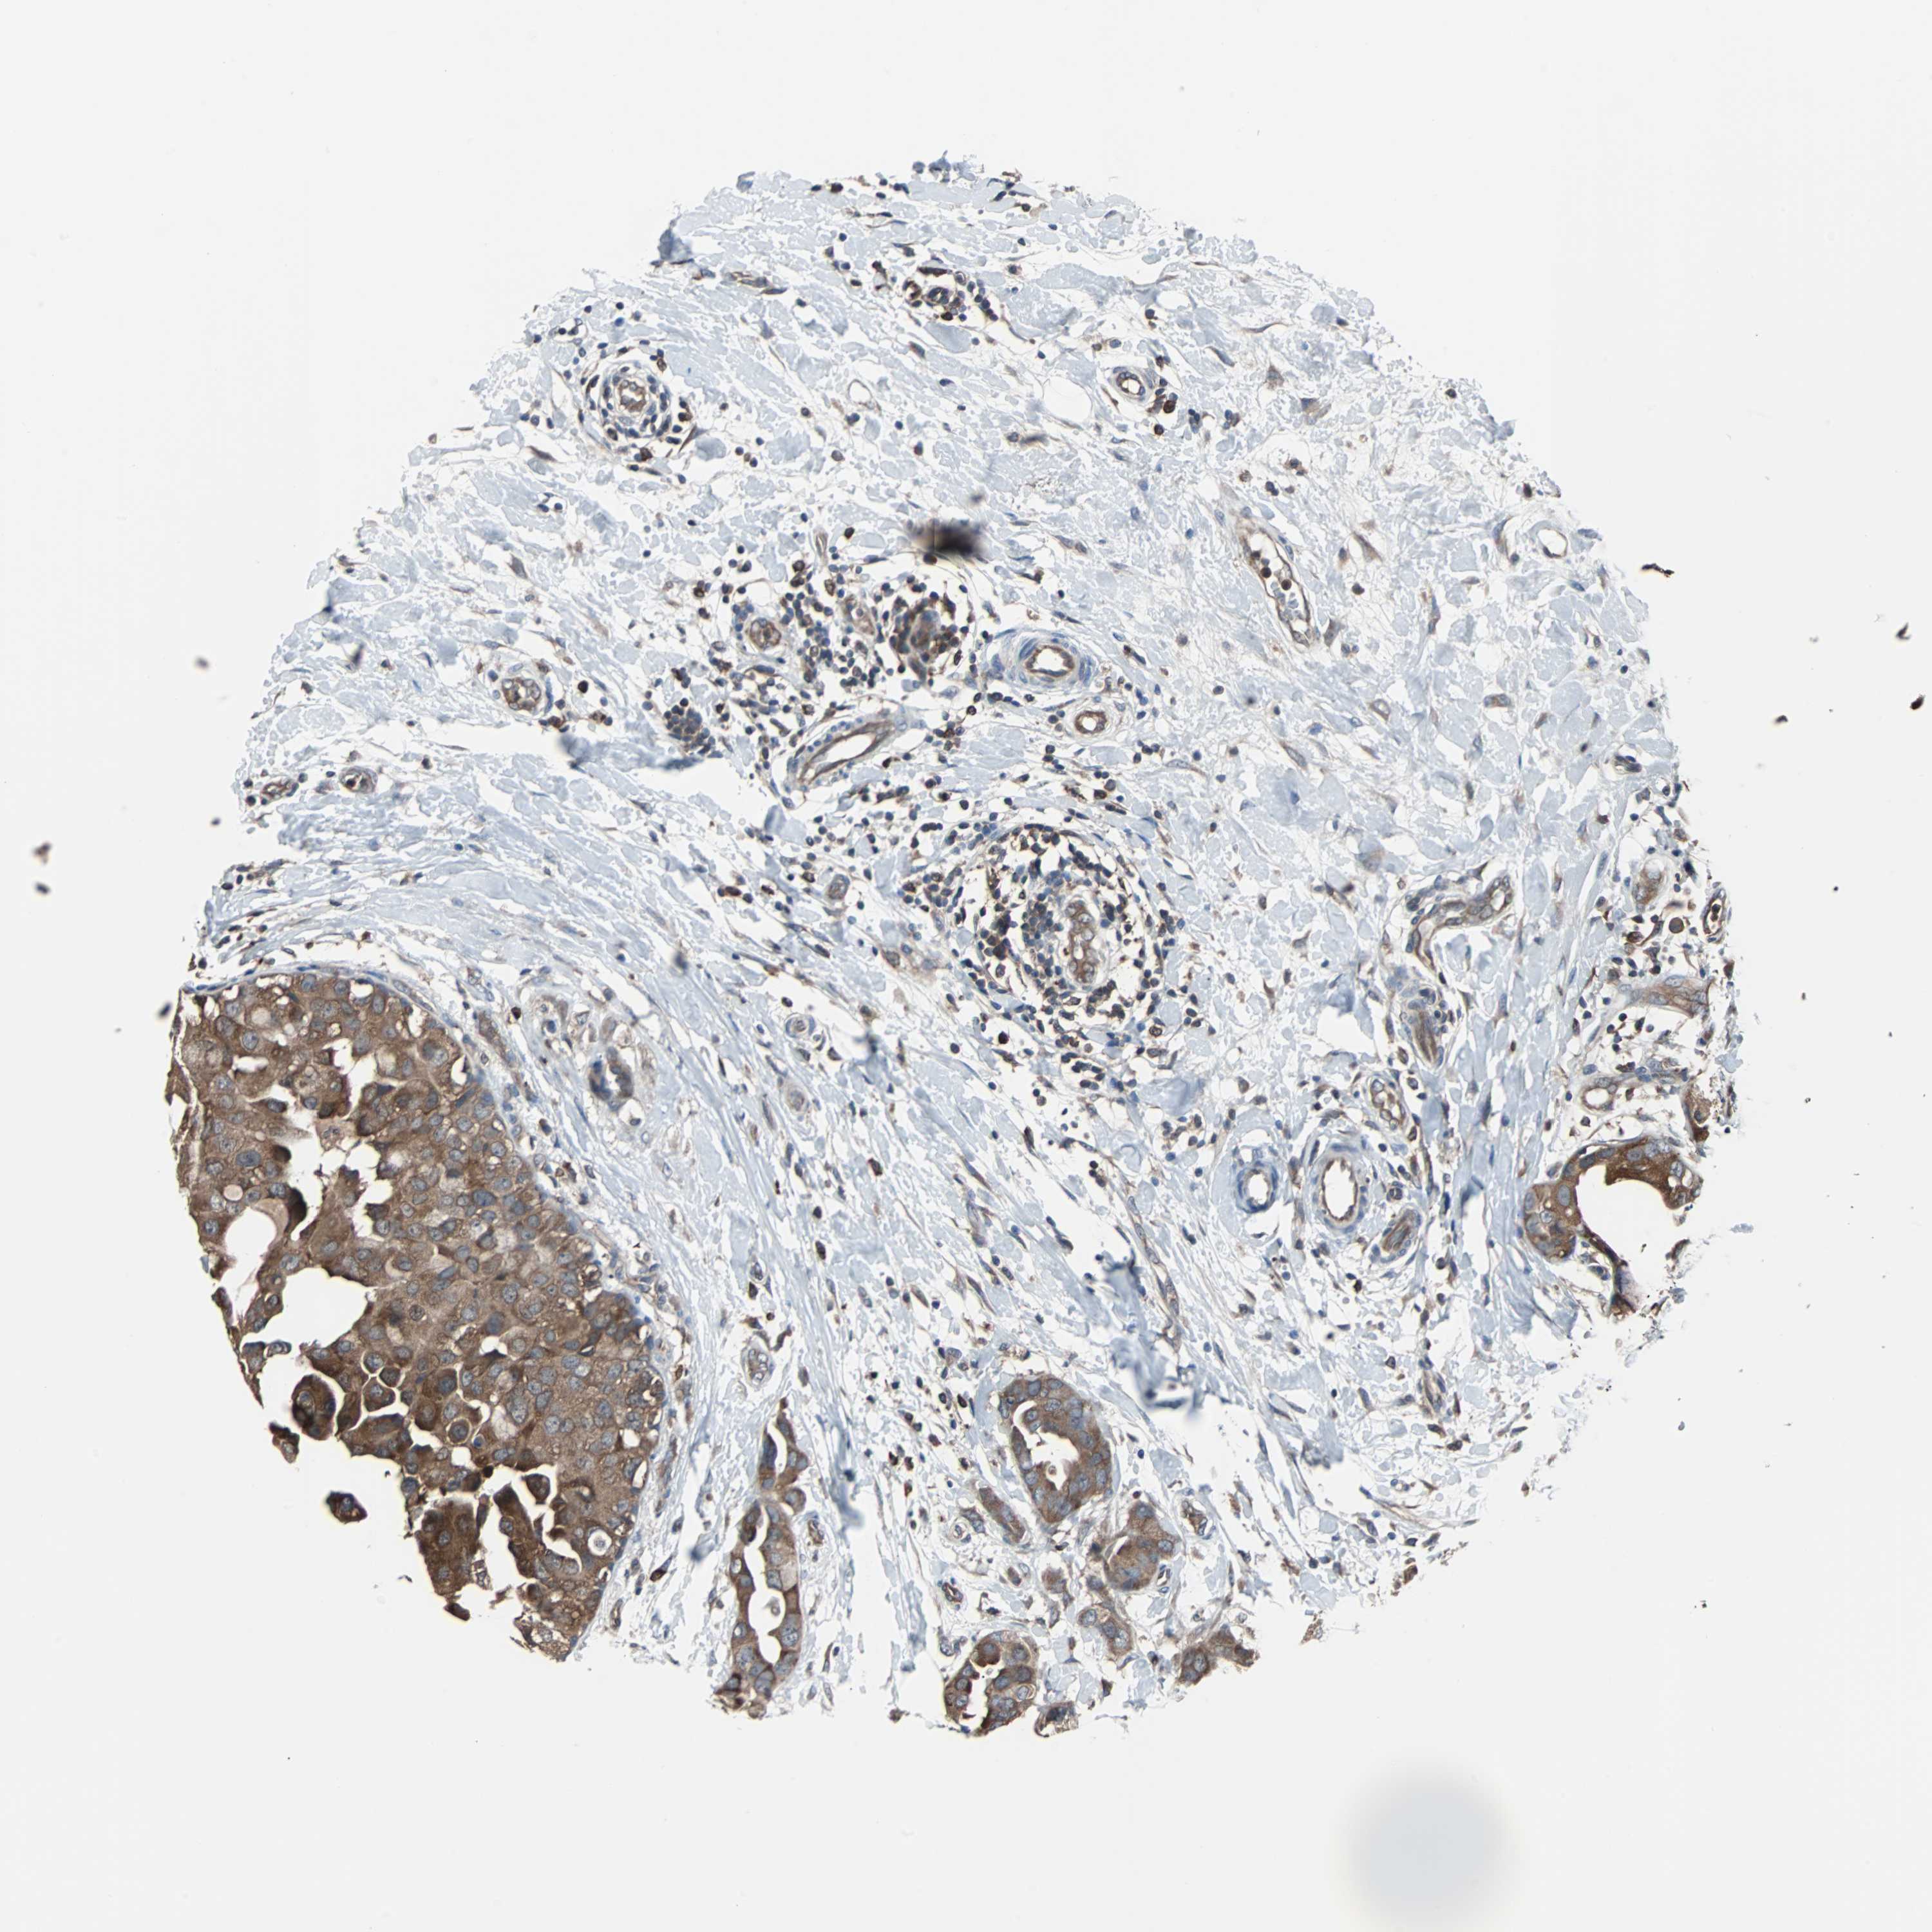

BRCA TCGA BRCA VALIDATION PROTEIN EXPRESSION

ANTIBODIES

AND

VALIDATION